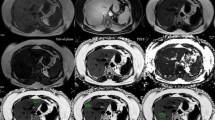

Analysis of liver segments

LFCs calculated in all hepatic segments (Fig. 3) are summarised in Table 2 for patients with and without steatosis.

Box plots of liver steatosis according to each hepatic segment (Couinaud classification). The top and bottom of the boxes are the first and third quartiles, respectively. The length of the box thus represents the interquartile range within which 50 % of the values were located. The line through the middle of each box represents the median. The error bars show the minimum and maximum values (range). An outside value (circles) is defined as a value that is smaller than the lower quartile minus 1.5 times the interquartile range, or larger than the upper quartile plus 1.5 times the interquartile range

Steatosis of the left and right liver was not homogeneous at the segmental level. In patients without liver steatosis, LFC in the left and right liver was heterogeneous (P < 0.001 and P < 0.0001, respectively). In patients with liver steatosis, LFC in the left and right liver was also heterogeneous (P < 0.0001 and P = 0.0002, respectively).

In the whole population, the average maximum difference in LFC between segments was 3.98 % (range: 0.74-19.32 %) (Fig. 4). This maximum difference between segments was greater than 5.56 % in 30 patients (24.8 %), while it was greater than 10 % in 5 patients (4.1 %). In 23 patients (19 %), LFC was <5.56 % in one segment, whereas it was ≥5.56 % in at least one other segment, which could account for a misdiagnosis of liver steatosis in cases when LFC is determined in one segment only.

At the segmental level, steatosis is heterogeneous in both the left and right liver as well. A mean maximum difference between segments of 3.98 % was reported over a wide range (0.74–19.32 %). This value cannot be ignored since it is close to the 5.56 % cutoff used for the diagnosis of steatosis. In most papers, monovoxel 1H-MRS is used to determine LFC in one segment, based on the argument that it is not subject to the sampling bias of liver biopsy [7, 14]. In our series, the segmental heterogeneity of steatosis may account for a misdiagnosis of steatosis in 19 % of patients. Therefore, all imaging techniques measuring steatosis in only one segment are also prone to sampling error given the segmental variability of steatosis. Interestingly, segment I has the lowest LFC among all the liver segments. Some non-tumorous defects of portal perfusion described in segment I have been reported to be caused by nonportal venous return from gastric arterial arteries [29], namely the parabiliary venous system. The parabiliary venous system originates from the pancreatico-duodenal and pyloro-duodenal veins, runs along the common bile duct and divides in the liver hilum [30]. Couinaud reported that the parabiliary system supplied segment I in 44.6 % of cases [30]. Decreased portal inflow due to non-portal blood supply via the parabiliary venous system might explain why there is less fat in segment I.